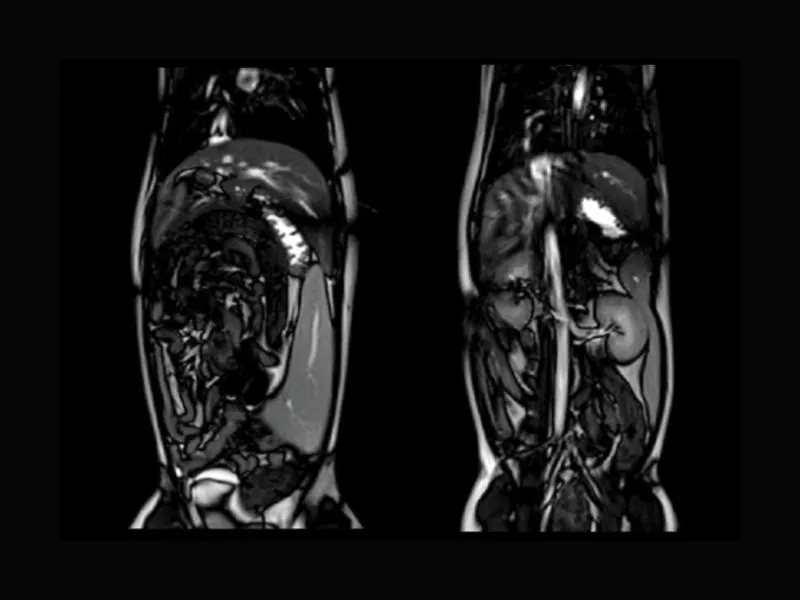

Supreme vet-mr – T2W of canine abdomen with respitarory gating